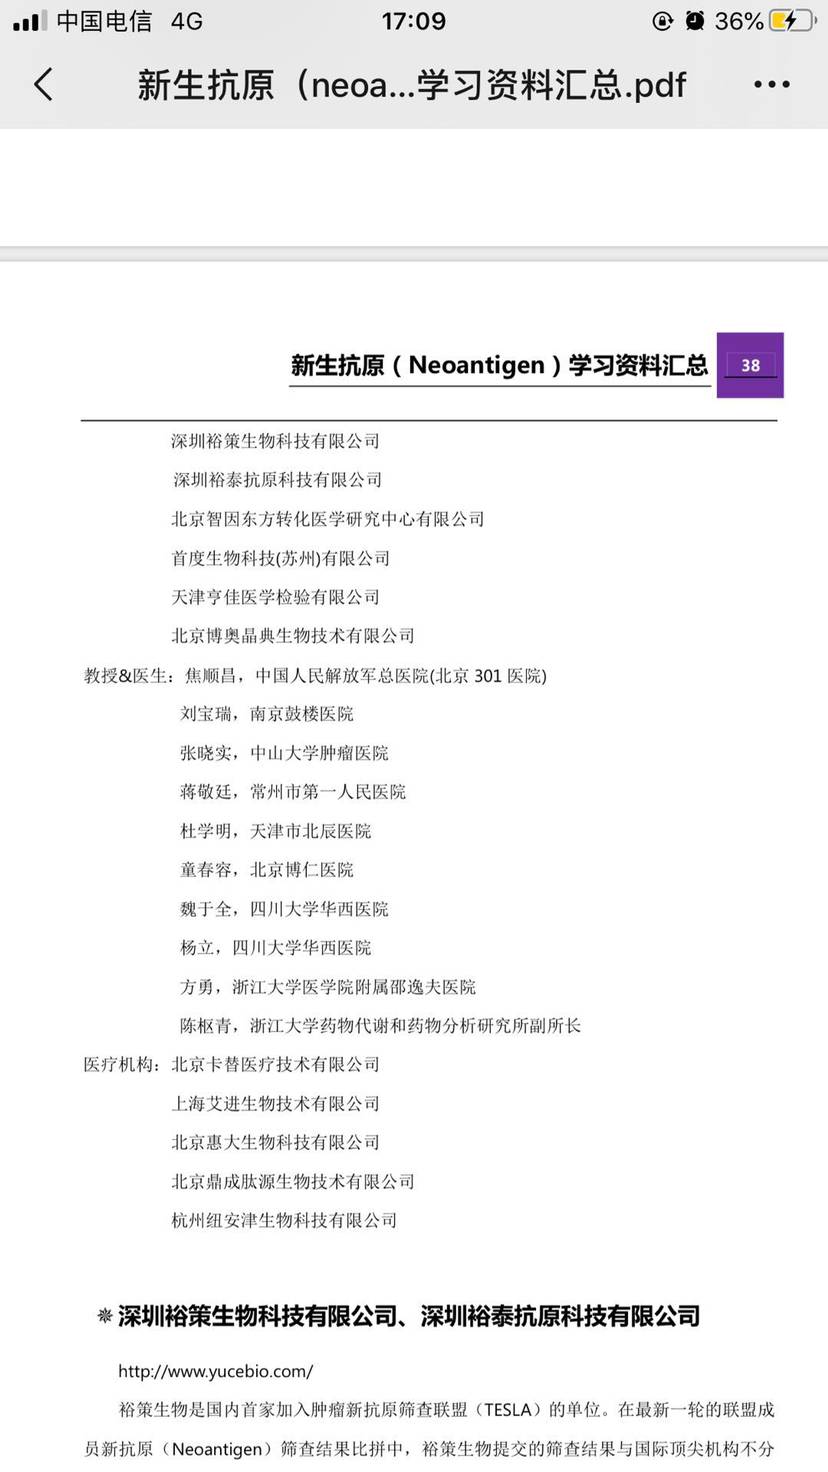

国内的研究机构和专家,大家可以咨询一下